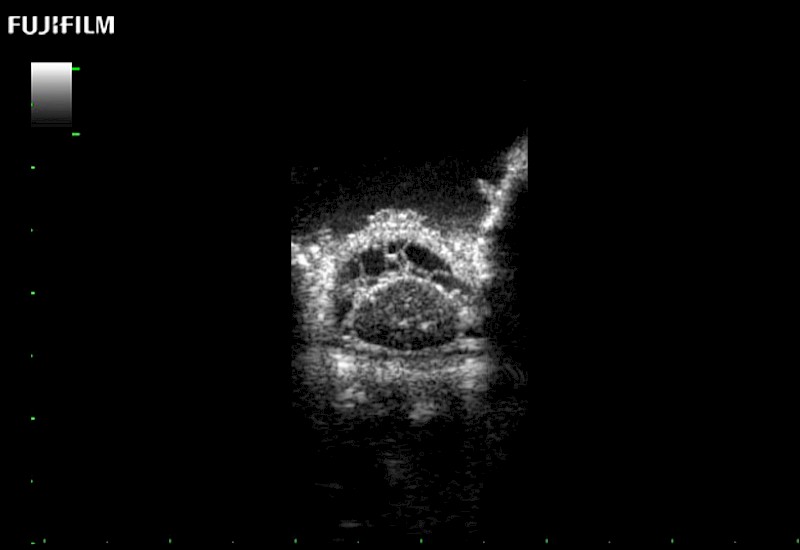

Tight curved (12mm) array transducer that is ideal for scanning during cranial guidance procedures.

The world's only phased array burr-hole transducer that is ideal for scanning during burr-hole guidance procedures.

Smaller footprint (20mm) curved array transducer that is ideal for scanning during cranial guidance procedures.

Exclusive 10mm side‐fire linear array transducer with 2.87mm diameter is ideal for real‐time visualization through and behind structures and instant, scalable definition of anatomy and vascularity including the ability to delineate and define tumor margins.